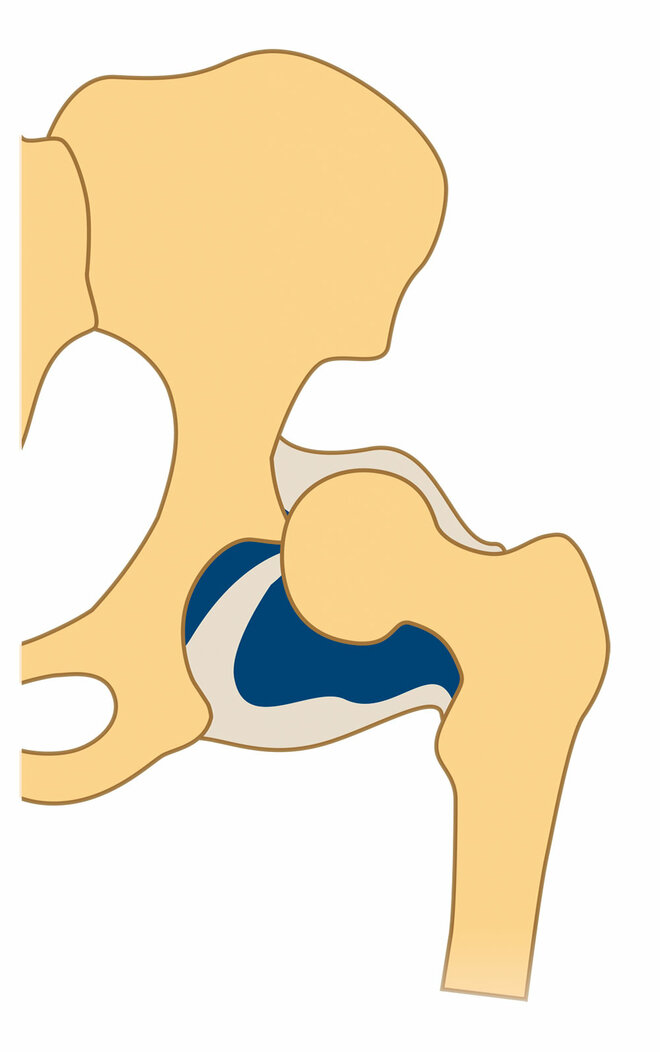

In den meisten Fällen löst sich das Problem in den ersten Lebenswochen von alleine. Bei etwa einem Prozent aber, sagt Ziegler, bleibe eine mehr oder weniger ausgeprägte Fehlstellung und Störung der Knochenreifung bestehen. Und bei maximal einem weiteren Prozent sei sie so stark, dass der Hüftkopf aus der Pfanne zu springen droht oder bereits gesprungen ist (siehe Infografik unten).

Drei Formen der Hüftreifestörung

Was der Orthopäde anspricht, ist die schwerste Form der sogenannten Hüftdysplasie, die Hüftluxation: Der Hüftkopf steht außerhalb der -pfanne und muss zurückgebracht werden. Funktioniert das ambulant nicht, wird das Kind stationär aufgenommen. "Bei uns in der Klinik haben wir – wenn nötig – mit der sogenannten Overhead-Extension eine sehr schonende, schmerzlose Methode zur Verfügung", sagt Ziegler. Dabei liegt das Kind auf dem Rücken, während seine Beine an Seilen und gespreizt in die Luft gezogen werden. "Sie können strampeln, und irgendwann rutscht der Hüftkopf in die Pfanne", so Ziegler.

Danach legen Ärzte dem Kind in Narkose einen Becken-Bein-Gips in Sitz-Hock-Stellung an. Dadurch kann die Hüfte nicht mehr ausrenken und in der richtigen Stellung so nachreifen, dass sie stabil ist.